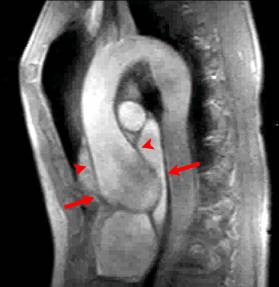

Answer: C. Aortic regurgitation and stenosis. There is both a stenotic jet which extends from the aortic valve into the ascending aorta during systole (arrow) as well as a smaller regurgitant jet extending from the aortic valve into the LV during diastole (arrowhead). Notice how there is minimal opening of the valve leaflets during systole, resulting in aortic stenosis. The right ventricle is not hypertrophied. With a ventricular septal defect, flow would be between the ventricles, which is not seen in this case. The severity of regurgitation or stenosis can be determined by the amount of signal void. Cardiac MRI has 98% sensitivity and 95% specificity for identification of aortic and mitral regurgitation. Higgins CB, Byrd BF, Stark D, et al. Diagnostic accuracy and estimation of the severity of valvular regurgitation from the signal void on cine magnetic resonance imaging. Am Heart J 1989; 118: 760-767.2) This inversion recovery sequence was taken 10 minutes after the administration of IV gadolinium. Which of the following entities does it show? ![]() Answer: B. DHE consistent with myocarditis. The image shows DHE (arrow) along the inferolateral wall of the left ventricle epicardium. The subendocardium is normal in this region. This finding is consistent with myocarditis as opposed to myocardial infarction in which DHE always involves at least the subendocardium. The structure within the left ventricular cavity is a normal papillary muscle seen in cross-section, not a thrombus or tumor. Laissy JP, Hyarfil F, Feldman LH, et al. Differentiating acute myocardial infarction from myocarditis: diagnostic value of early- and delayed- perfusion cardiac MR imaging. Radiology 2005; 237 (1):75-82.3) This horizontal long axis SSFP demonstrates which of the following entities? Answer: A. Apical septum wall motion abnormality. This cine shows a localized abnormality of the apical septum (arrow). The myocardium in this area does not thicken as much as the surrounding myocardium. When necessary, wall thickening can be quantified to assess region wall motion abnormalities. The remainder of the left ventricle functions normally, so global systolic of diastolic function is not present. Azhari H, Sideman S, Weiss JL, et al. Three-dimensional mapping of acute ischemic regions using MRI: wall thickening versus motion analysis. Am J Physiol 1990; 259:H1492-503.4) What are the primary physiologic consequences of the entity in the image shown below? ![]() Answer: C. Restricted diastolic filling and increase in venous pressures. The figures shown above are T1-weighted and T1-weighted with fat saturation images. The images show a pericardium that is thicker than 3 mm (arrows). This finding is consistent with constricted pericarditis in the appropriate clinical setting. Axel L. Assessment of pericardial disease by magnetic resonance and computed tomography. Journal of Magnetic Resonance Imaging 2004; 19(6):816-26.5) The cine below shows findings which are characteristic of which of the following? Answer: C. Arrhythmogenic right ventricular cardiomyopathy. The above cine shows a heart with marked RV dysfunction (arrow) out of proportion to the LV. The other entities listed would be expected to affect primarily the LV. Bluemke DA, Krupinski EA, Ovitt T, et al. MR Imaging of arrhythmogenic right ventricular cardiomyopathy: morphologic findings and interobserver reliability. Cardiology 2003; 99(3): 153-62.6) The gradient echo cine below shows what congenital abnormality? Answer: A. Atrial septal defect. There is a clear defect (arrow) in the superior aspect of the interatrial septum between the right and left atria. None of the other abnormalities are seen in this image. Wang ZJ, Reddy GP, Gotway MB, Yeh BM, Higgins CB. Cardiovascular shunts: MRI imaging evaluation. Radiographics 2003;23 Spec No:S181-94.7) This spin echo image shows what aortic abnormality? ![]() Answer: D. Aortic coarctation. This image shows an irregular narrowing at the aortic isthmus just distal to the left subclavian (arrow). MRI is especially useful in assessing the aorta after coarctation repair to assess for restenosis and the degree of collateralization utilizing VENC imaging. Kellenberger CJ, Yoo S, Valsangiacomo Buchel ER. Cardiovascular MR Imaginging in Neonates and Infants with Congenital Heart Disease. Radiographics 2007;27:5-18.8) Which of the following is shown in the IR image below acquired 10 minutes following infusion of gadolinium contrast agent? ![]() Answer: B. Subendocardial infarct. This image shows delayed hyperenhancement of the inferoseptal, inferolateral wall, and lateral LV wall. The DHE involves the subendocardium (arrow) which is suggestive of infarction, as opposed to the mid myocardial or epicardial location in myocarditis. The DHE does not involve the entire wall however, so it is a subendocardial as opposed to transmural infarct. A ventricular aneurysm would show a focal bulge of ventricular wall. Wu E, Judd RM, Vargas JD, Klocke FJ, Bonow RO, Kim RJ. Visualization of presence, location, and transmural extent of healed Q-wave and non-Q-wave myocardial infarction. Lancet 2001; 357 (9249): 21-8.9) The cine image below uses a technique specialized to determine what entity? Answer: C. Myocardial strain. This cine image uses a special modulation of magnetization to produce tag lines that move with the myocardium. The degree of deformation of the squares is used to calculate myocardial strain, which gives an accurate (sensitivity 92%, specificity 99%) quantitative assessment of myocardial function. A series of non-tagged short axis images can be used to measure ejection fraction, end-systolic volume and myocardial mass. Myocardial perfusion imaging uses gadolinium and adenosine. Gotte MJW, van Rossum AC, Twisk JWR, et al., Quantification of regional contractile function after infarction: strain analysis superior to wall thickening analysis in discriminating infarct from remote myocardium. J Am Coll Cardiol 2001; 37: 808-817.10) Which congenital cardiac anomaly is shown on the gradient echo cine below? Answer: A. Ebstein’s anomaly. In Ebstein's anomaly, the septal and posterior leaflets of the tricuspid valve (arrows) are displaced apically resulting in atrialization of the base of the right ventricle. The tricuspid annulus, however, is normally positioned between the right atrium and ventricle. The atrialized portion of the RV is thinned and prone to aneurysmal dilation. There is no connection between the two sides of the heart that would suggest a ASD or VSD. None of the findings of Tetralogy of Fallot are present. The pulmonic valve and aortic arch are not visualized in this slice. Choi YH, Park JH, Choe YH, et al. MR imaging of Ebstein’s anomaly of the triuspid valve. Am J Roentgenol 1994; 163:539-43.11) Below are pre and post gadolinium SSFP images. What abnormality do they show? ![]() Answer: D. Thrombus. The mass in the LV does not enhnance on post-contrast imaging, which is consistent with a thrombus. Thrombi form in regions of akinesis, typically due to myocardial infarctions. Microvascular obstruction is a process which involves the myocardium. Myxomas and metastatic disease typically have a heterogenous appearance and enhance. Papillary muscles enhance with myocardium. Friedrich MG. Magnetic resonance imaging in cardiomyopathies. J Cardiovasc Magn Reson 2000;2:67-82.12) Which of the following is seen on the gradient echo cine below? Answer: B. Pericardial effusion causing cardiac tamponade. There is a large amount of fluid in the pericardial sac (arrows). This fluid is physiologically significant because the contractile function of the heart is compromised and there is diastolic collapse of multiple chambers. The fluid is within the pericardium surrounding the heart, thus excluding pericardial cyst. The pericardium is not thickened, essentially excluding constrictive pericarditis. This diagnosis is usually made with echocardiography. Bilateral pleural effusions are also present. Wang ZJ, Reddy GP, Gotway MB, Yeh BM, Hetts SW, Higgins CB. CT and MR imaging of pericardial disease. Radiographics 2003; 23: S167-80.13) What abnormality is seen in this cine? ![]() Answer: C. Delayed hyperenhancement of hypertrophic cardiomyopathy. The DHE vertical long axis image demonstrates regional hypertrophy of the myocardium in the anterior wall (arrows) which is consistent with hypertrophic cardiomyopathy. There is also subepicardial and mid-myocardial delayed enhancement in the region of the hypertrophy which is due to fibrosis. Rickers C, Willke NM, Jero-Herlold M, et al. Utility of cardiac magnetic resonance imaging in the diagnosis of hypertrophic cardiomyopathy. Circulation 2005; 112(6):855-61.14) What abnormality is seen on the SSFP vertical long axis cine seen below? Answer: A. Myxoma. This cine shows a myxoma (arrow) within the left atrium that is partially prolapsing through the mitral valve. Myxomas are most often located in the left atrium, often pedunculated, and commonly attached to the interatrial septum. When large, they can obstruct the mitral valve and cause symptoms of mitral stenosis. Myxomas are well encapsulated unlike angiosarcomas which are a malignant tumor and are very invasive. A lipoma should have the same signal as subcutaneous fat, therefore it would be much brighter than this mass. This would be an unusual location for an intracardial thrombus, which typically form in areas of minimal motion. Sparrow PJ, Kurian JB, Jones TR, Sivananthan MU. MR Imaging of cardiac tumors. Radiographics 2005; 25(5): 1255-76.15) Below are perfusion images of basal, mid, and apical slices along with a delayed hyperenhancement image (bottom) aligned with the mid slice. The resting images are displayed on the top left with the Adenosine images displayed in the top right. What abnormality is seen in these images?